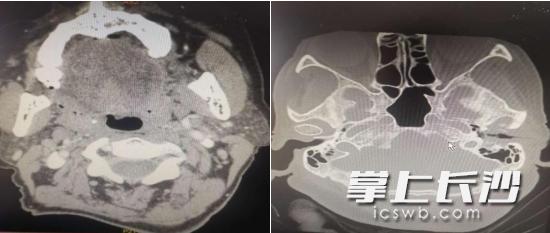

术前颞骨CT检查片

刘国辉给李女士做了仔细的体格检查,CT考虑外耳道软组织肿块,考虑外耳道癌可能性大;耳内镜下发现其左侧外耳道外侧及下壁菜花样新生物,触之易出血,结合首次的病理切片,经医院病理科会诊确诊为外耳道癌,手术刻不容缓。